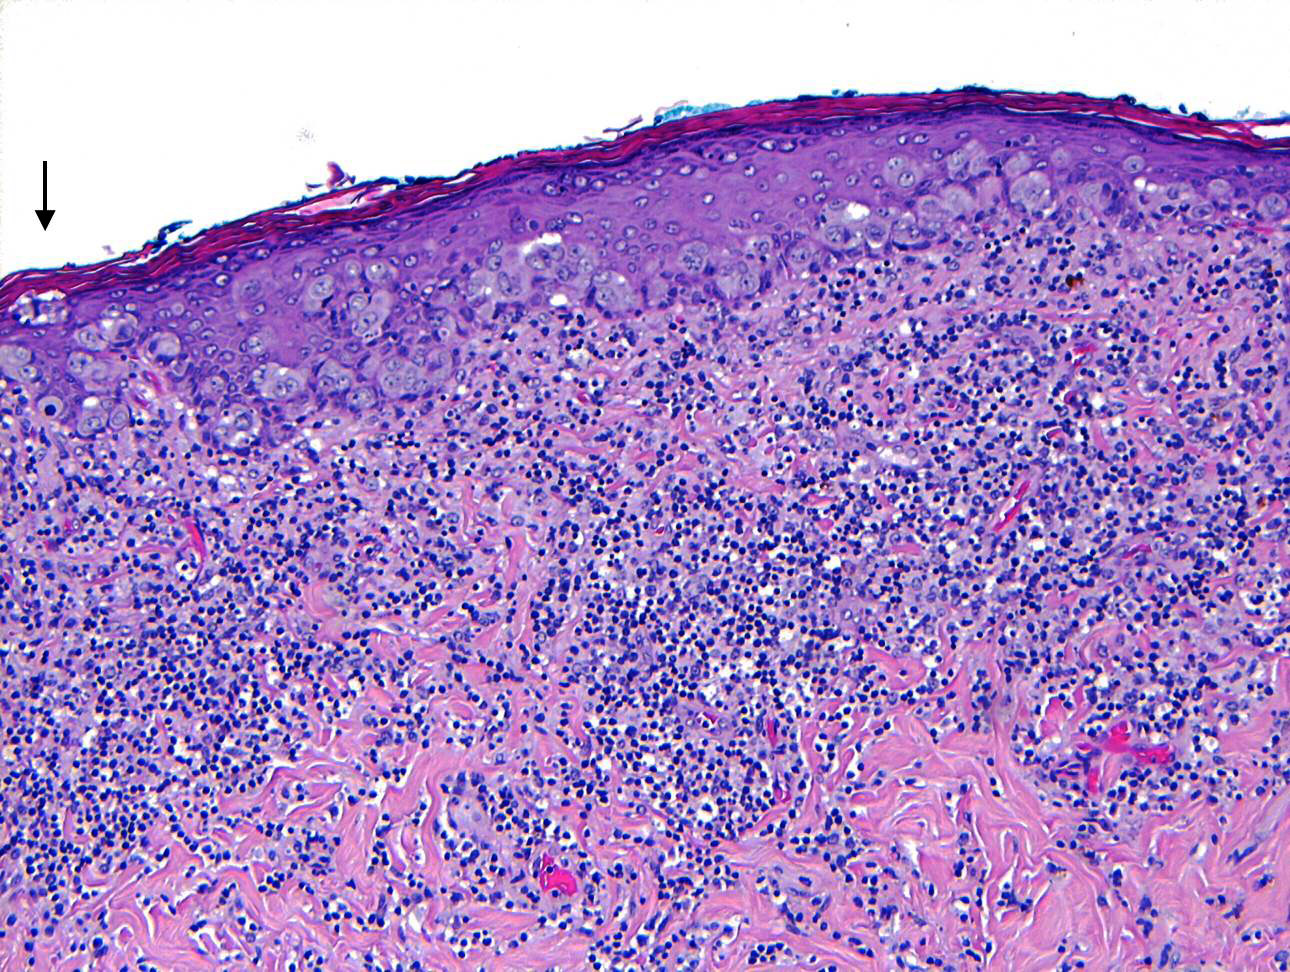

- Single cells or clusters of cells spread throughout the epidermis

- Cells have abundant pale cytoplasm, large irregular nuclei with prominent nucleoli

- Underlying dermis may have chronic inflammation

- Epidermis with hyperkeratosis and possibly ulceration

- Florid cases can show gland formation

- Paget cells may phagocytose melanin, mimicking melanocytes

- Underlying carcinoma is most commonly high grade invasive carcinoma of no special type (NST; 53 - 64%) or DCIS (24 - 43%) (Histopathology 2020;77:181)

Microscopic (histologic) images

Contributed by Anna Biernacka, M.D., Ph.D. and Mary Ann Gimenez Sanders, M.D, Ph.D.